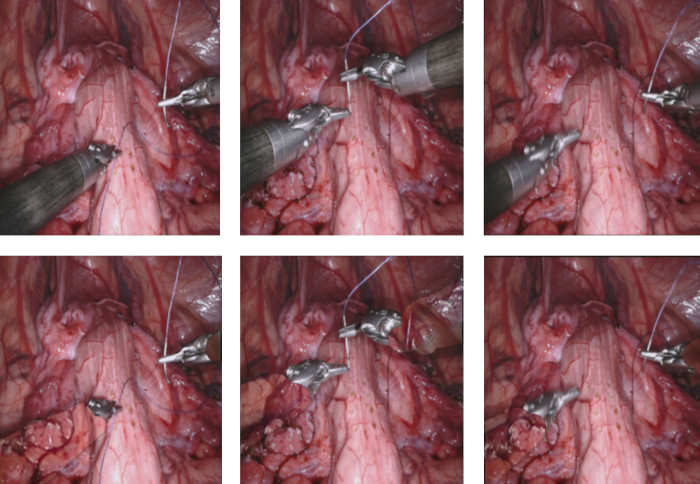

Occlusion reconstruction for MIS sequences

Occlusion reconstruction for MIS sequences. Top row is the original video broken down into sequential images and the bottom row is the same image regenerated by this proposed AI model with the object removed.